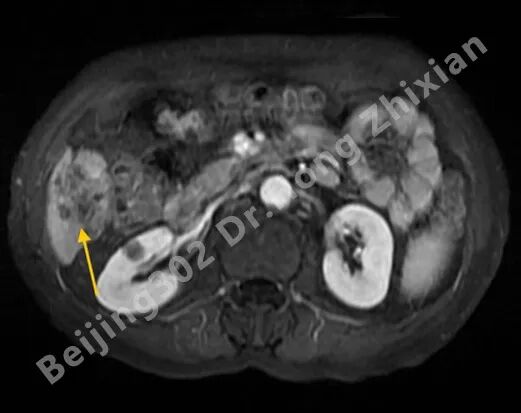

临床随笔丨肝癌术前新辅助治疗:“更优选择”还是“过度治疗”?

病例简介